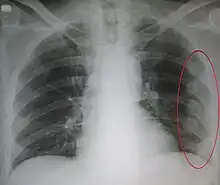

Right sided pneumothorax and rib fractures